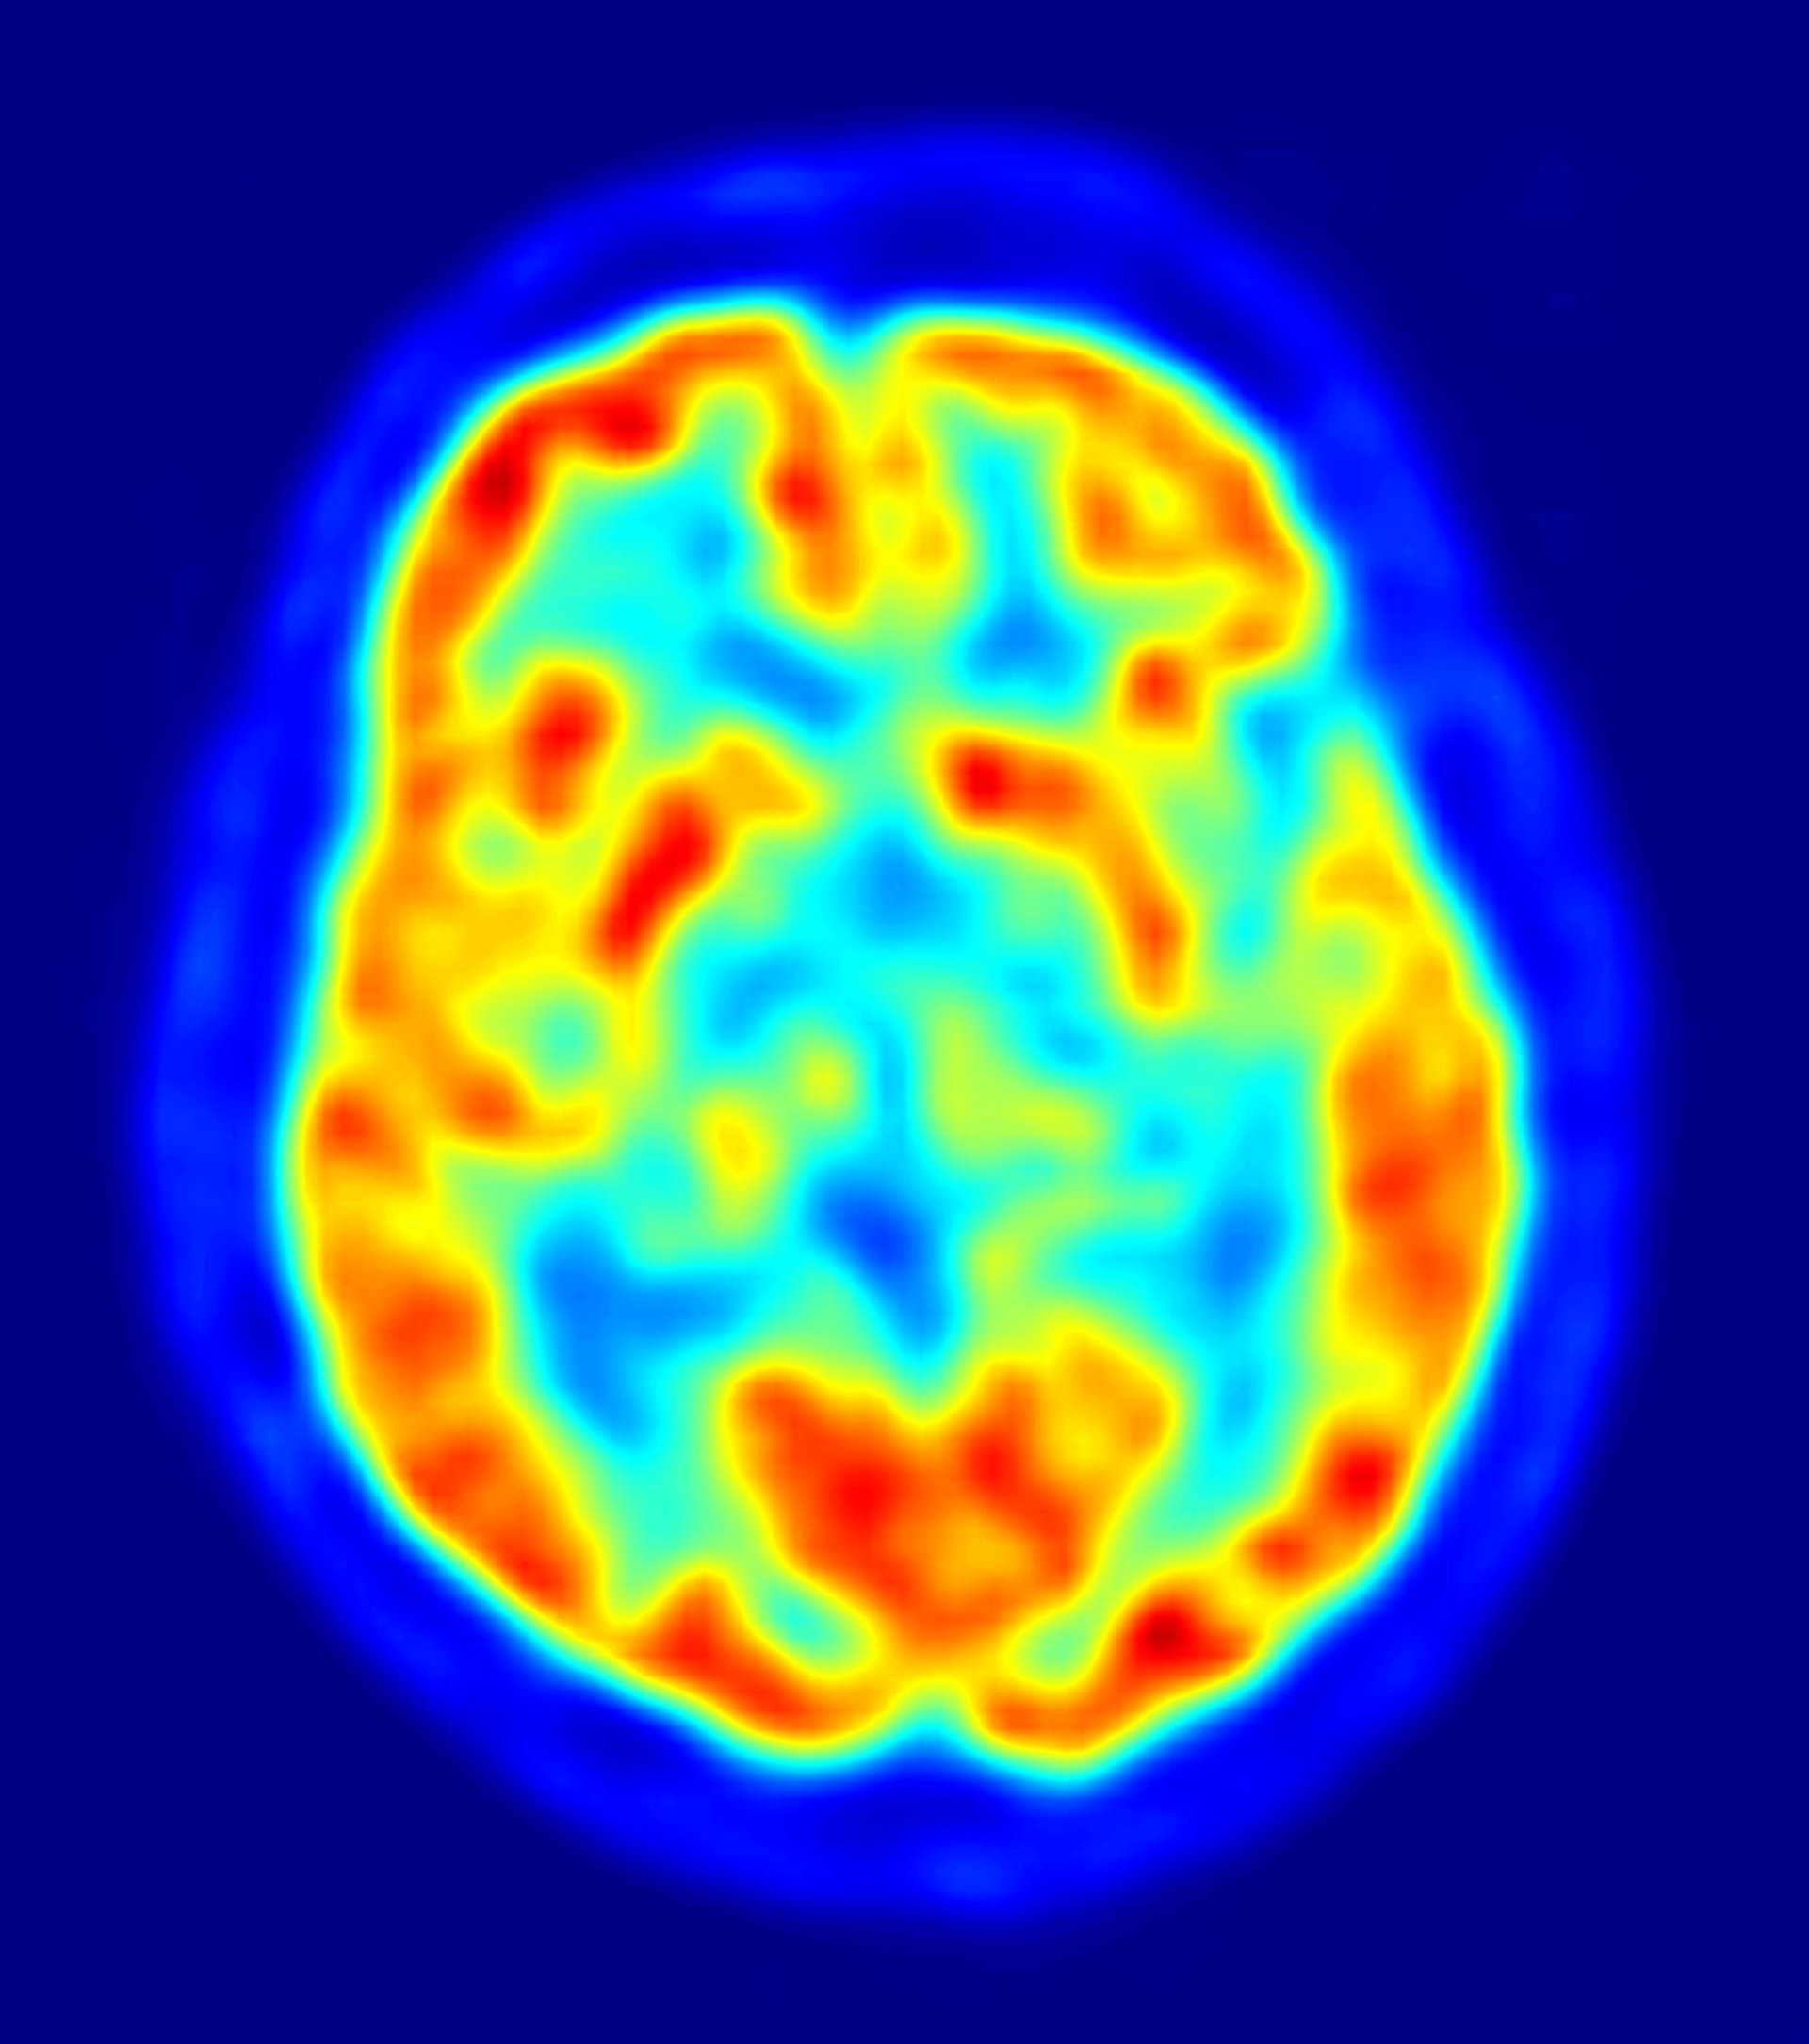

cerebro, recurso, neuronas

La enfermedad de Alzheimer, la forma más común de demencia, es un trastorno neurodegenerativo con una alta prevalencia entre los mayores.

Los trabajos así subrayan mecanismos moleculares que podrían estar implicados en la neurodegeneración y la eliminación en el cerebro del amiloide beta, el principal constituyente de las placas amiloides que se forman en el cerebro y que caracterizan a la enfermedad de Alzheimer.